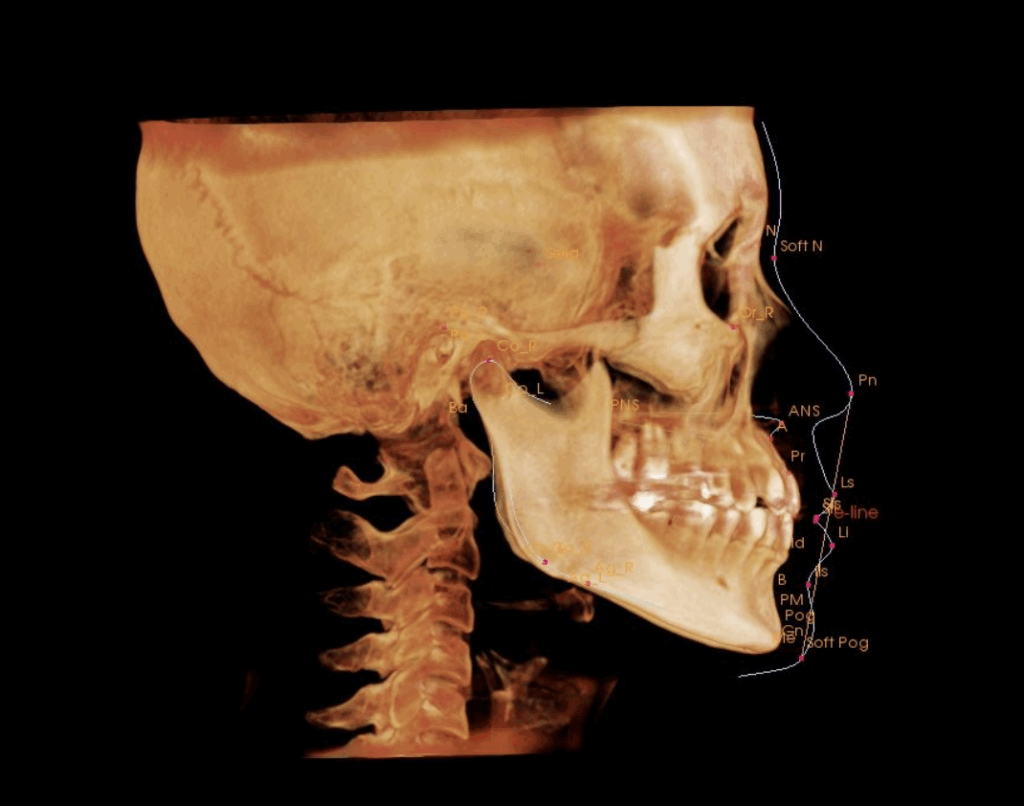

セファロ分析(横顔の骨格バランスを確認)

矯正治療の診断に欠かせないのが、セファロ分析(頭部X線規格写真)です。

この分析によって、横顔の骨格バランスや歯の傾きを正確に評価することができます。

この方の分析では、

垂直的なバランス(顔の上下の長さ)には、やや短い

水平的(前後的)には、やや下顎前突の傾向 が見られました。

また、前歯の軸が内側に傾いていることも確認されました。

これは、下顎が前に出る骨格の方に見られやすい特徴で、

「前歯でかみ合うために、自然と歯が内側に傾く」傾向があります。

その結果、歯が並ぶスペースが不足し、**間の歯がガタガタ(叢生)**になりやすくなっていました。

つまり、骨格と歯の傾きの両方が、今回の「八重歯」をつくる要因になっていたことがわかります。